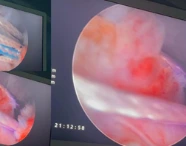

Postpartum Haemorrhage: A Case Series Highlighting Diverse Clinical Profiles and Evolving Management Strategies in a Tertiary Care Setting